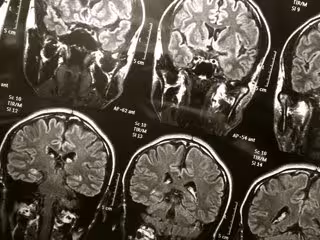

Descubren procesos clave en la respuesta del cerebro al trauma

Cerebro

FLICKR/WYINOUE